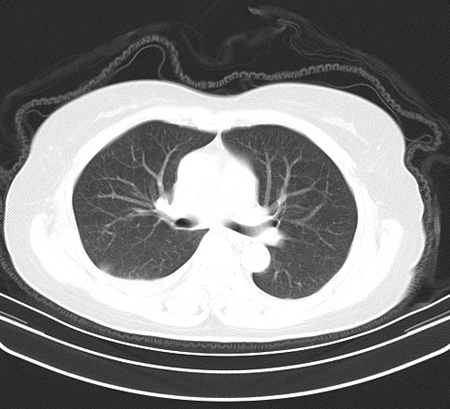

以下是引用余辉在2009-2-19 20:10:00的发言:[br]多考虑急性感染性病变,右中叶尚可见多枚小斑片状影,多为化脓性肺炎,双侧胸腔积液

以下是引用随光逐影在2009-2-19 20:33:00的发言:[br]1)考虑右肺炎症;建议抗炎治疗后复查。2)双侧胸腔积液(以右侧为甚)。

以下是引用花凤凰在2009-2-19 20:46:00的发言:[br]病人有发热,胸痛急性起病,主要病变位于右肺中叶外侧段,呈楔行改变,位于外带胸膜下,考虑为肺梗塞可能!!!!!!!!!!!!!!!!!!!!!!!!!!!!!!!!!!!